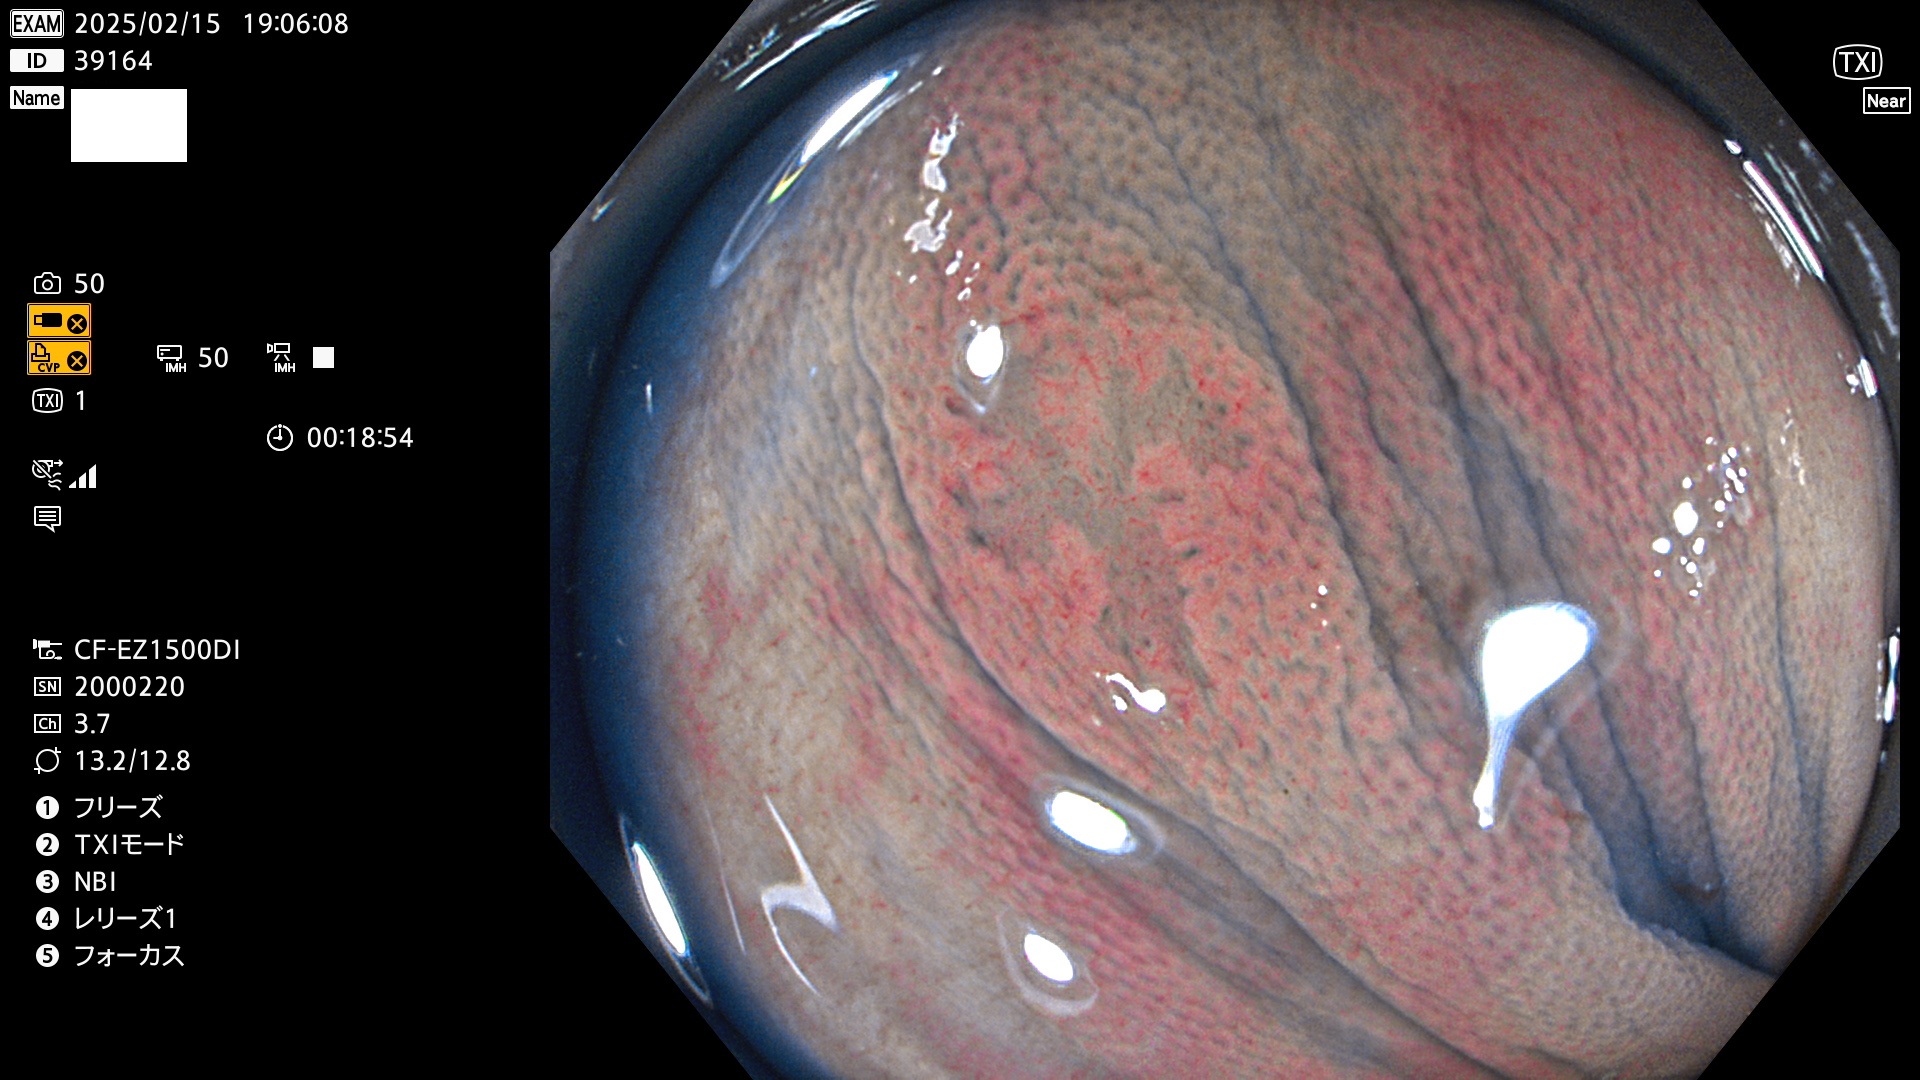

今週のUb、Uc型腺腫

完全に平坦な物をUb、陥凹している物をUcと呼びます。最も発見が難しく危険な病変です。

毎週の検査(木・金・土・日)に発見されたUb、Uc型・腺腫を、その週の日曜の夜にUPし1週間、提示します。

抽出の対象期間 2025年2月13日〜2月16日の4日間(48件の検査)8個 (8/48=16%)